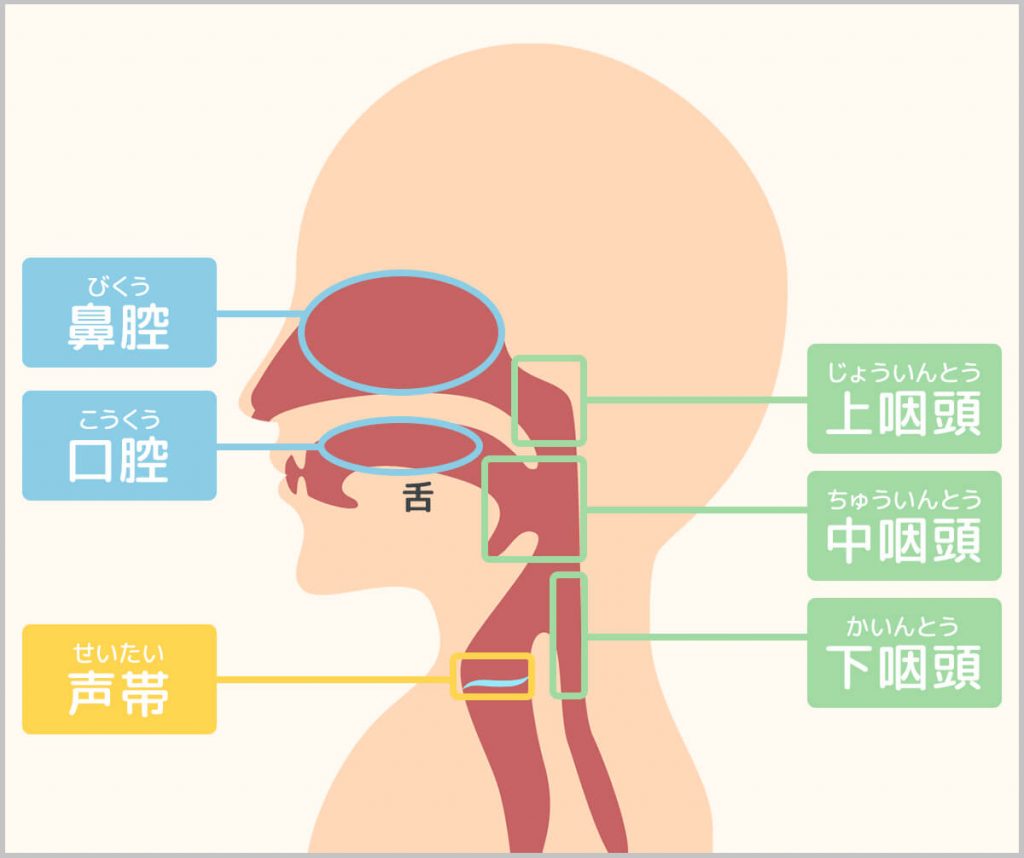

口から喉にかけての部位の名称(鼻腔・口腔・上咽頭・中咽頭・下咽頭・声帯)